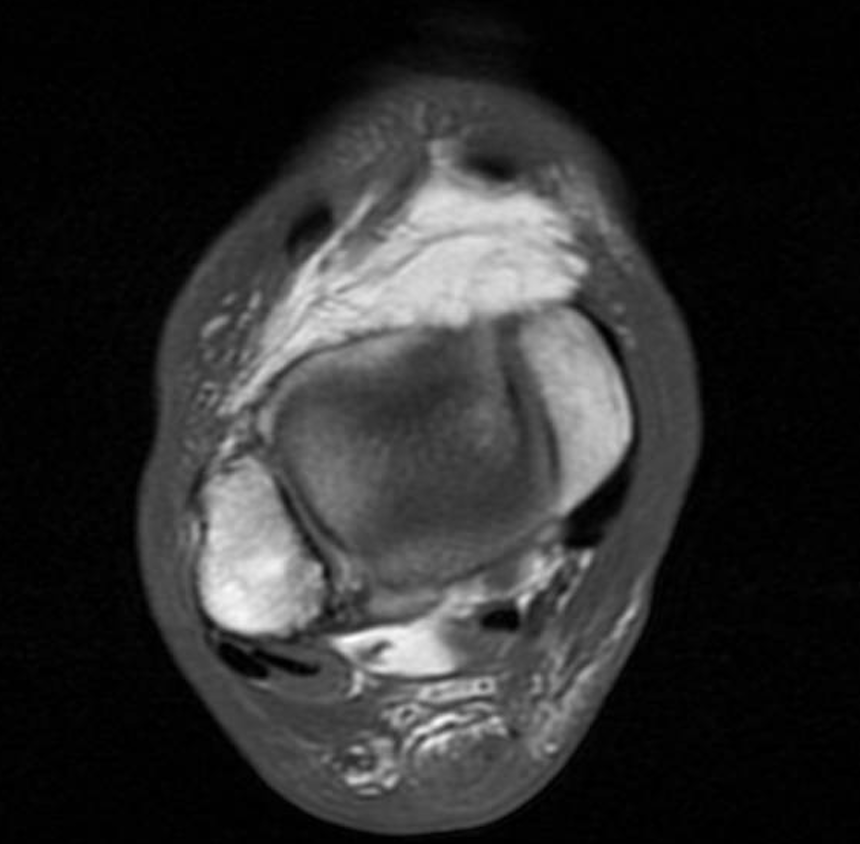

A physical exam revealed edema bilateral to the lower extremities with ecchymosis on the left side but not on the right lower extremity. The patient was neurovascularly intact, and the exam revealed a positive Thompson test on the bilateral lower extremities with no active ankle plantarflexion on the left and right sides. There was a palpable delve in the Achilles on both sides. An MRI that day on both lower legs revealed bilateral Achilles tendon ruptures with a left gap of 3.5cm and a right gap of 2.5 cm.